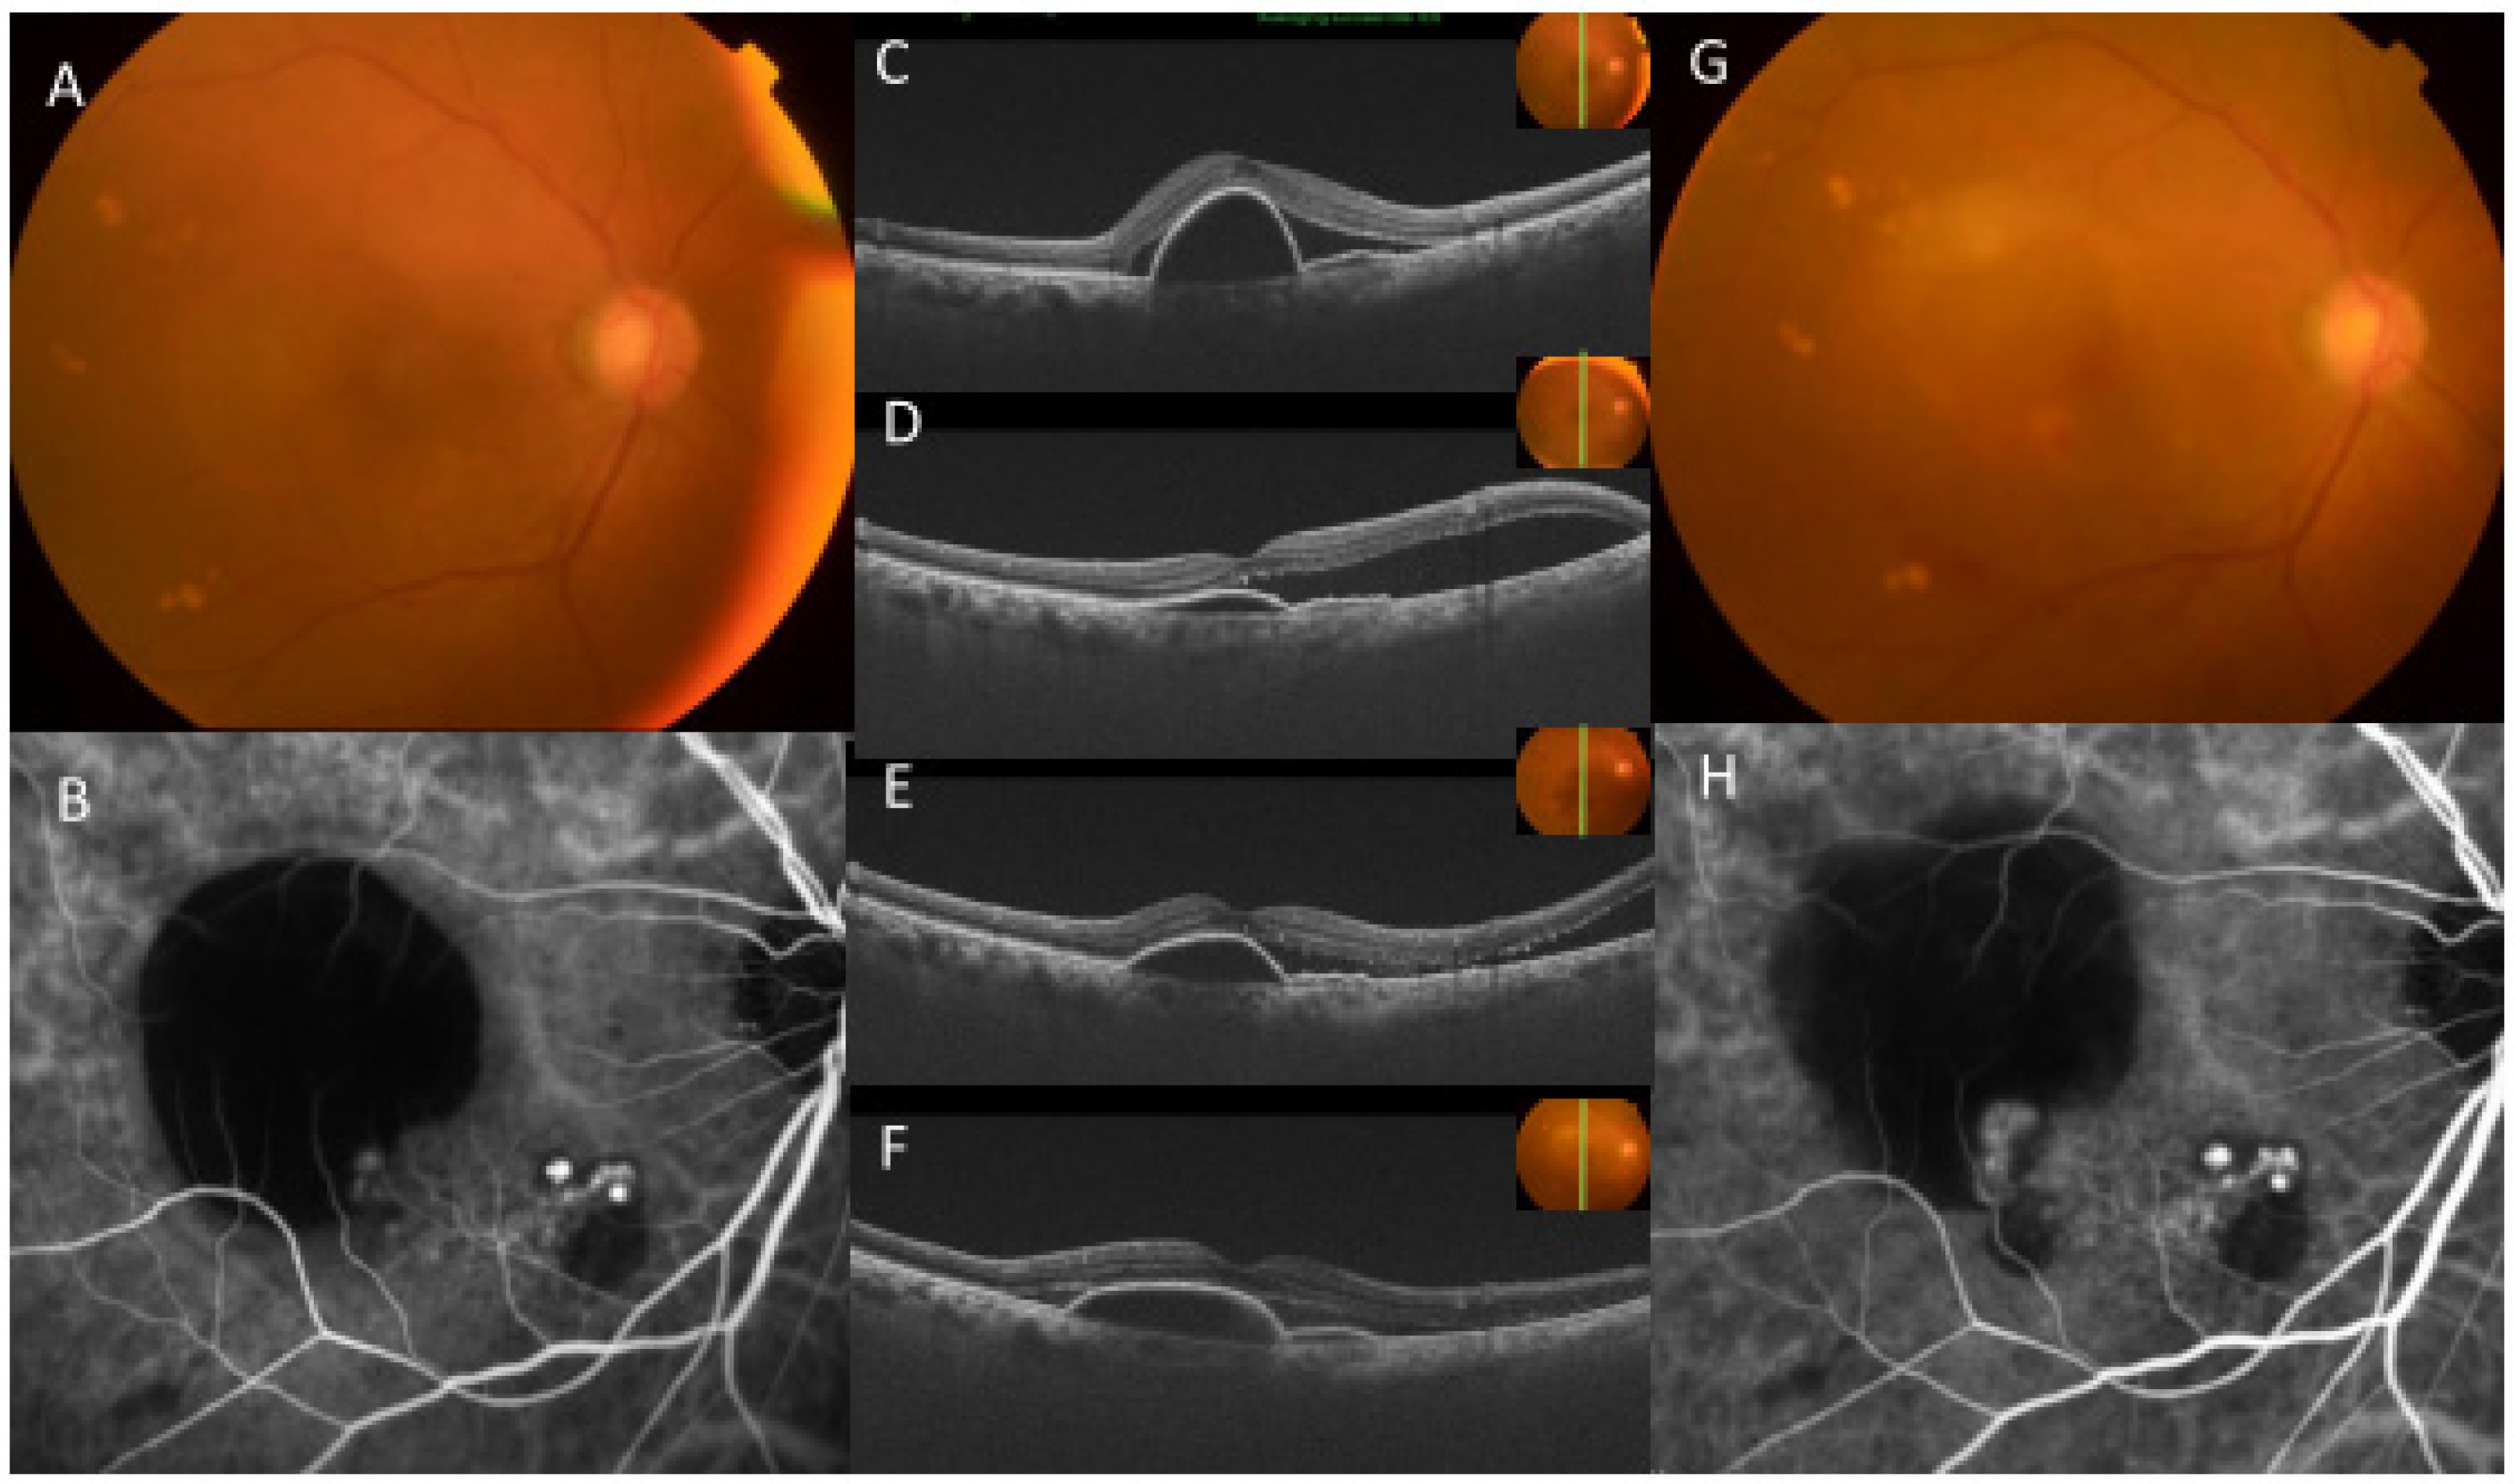

3. Results